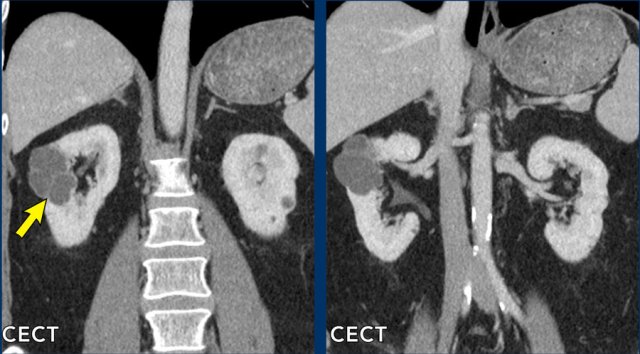

case 1

The images show a complex large right renal cyst with T1 and T2 hyperintense internal fluid and T1 hyperintense debris, which shows mild enhancement on the subtraction image.

This cyst also has an enhancing mural nodule (see arrow coronal images), classifying it as a Bosniak IV lesion.

The kidney was removed and the cyst represented a papillary renal cell carcinoma